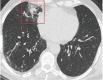

A new type of coronavirus (2019-nCoV) is rapidly spreading worldwide and causes pneumonia, respiratory distress, thromboembolic events, and death. Chest computed tomography (CT) plays an essential role in the diagnosis of viral pneumonia, monitoring disease progression, determination of disease severity, and evaluating therapeutic efficacy. Chest CT can show important clues of 2019-nCoV disease (also known as COVID-19) in patients with an appropriate clinic. Prompt diagnosis of COVID-19 is essential to prevent disease transmission and provides close clinical observation of patients with clinically severe disease. Therefore, radiologists and clinicians should be familiar with the CT imaging findings of COVID-19 pneumonia. Herein, we aimed to review the imaging findings of COVID-19 pneumonia and examine the critical points to be considered for imaging in cases with COVID-19 suspicion.